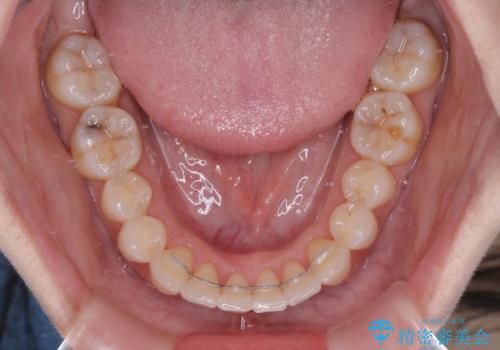

前歯のクロスバイト インビザラインによる矯正治療

- 上下のクロスバイトと前歯のデコボコを気にして来院された患者様です。

インビザラインを用い、IPR(歯と歯の間を削る)と歯列全体を拡大させることで、歯並びを整えていくこととしました。

治療を急いでいらっしゃらなかったため、のんびりと治療を進めていきました。3年以上の期間を要しましたが、きれいな口元に仕上がりました。